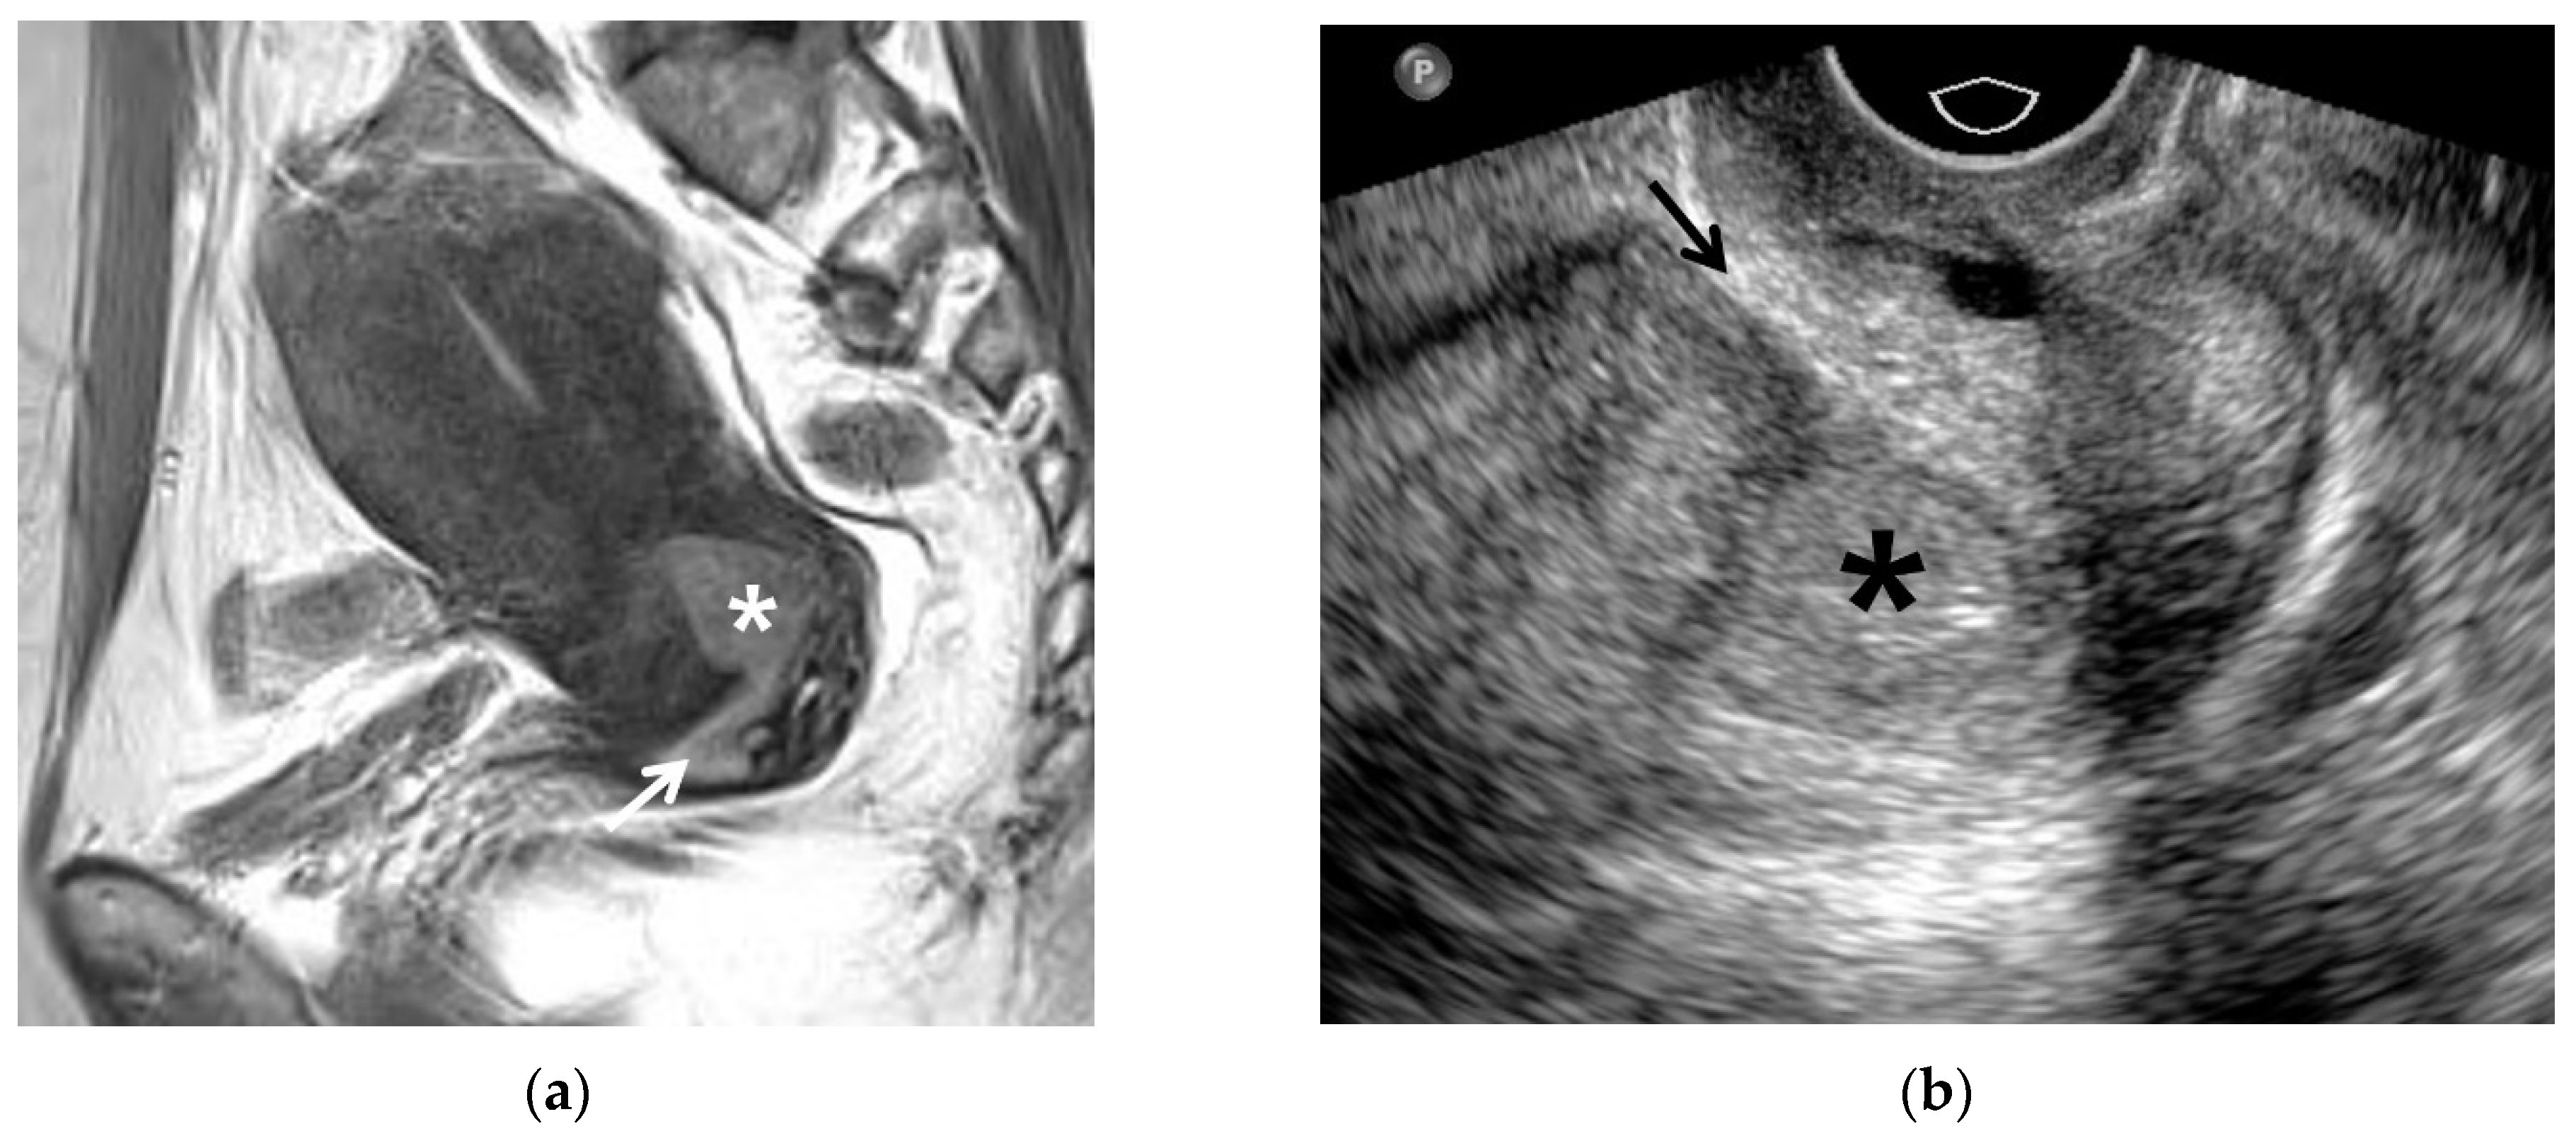

3.1. T2WI Findings

4. Post-Conization MRI